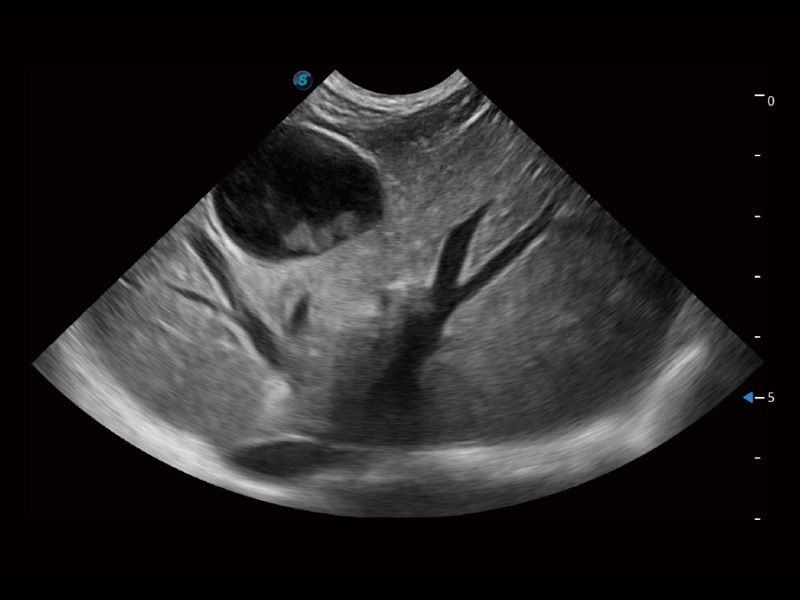

通过360度任意调节3条M型取样线,在同一心动周期上观察心脏不同位置的运动曲线,得到准确的心功能测量数据,有效评估心肌运动及左心室功能。